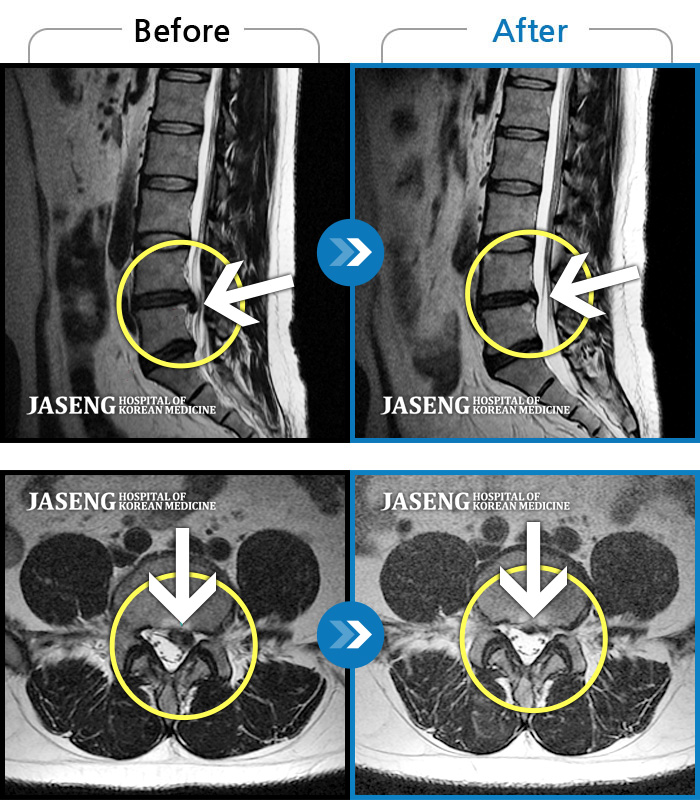

[뱸] 19.11.28~25.05.06